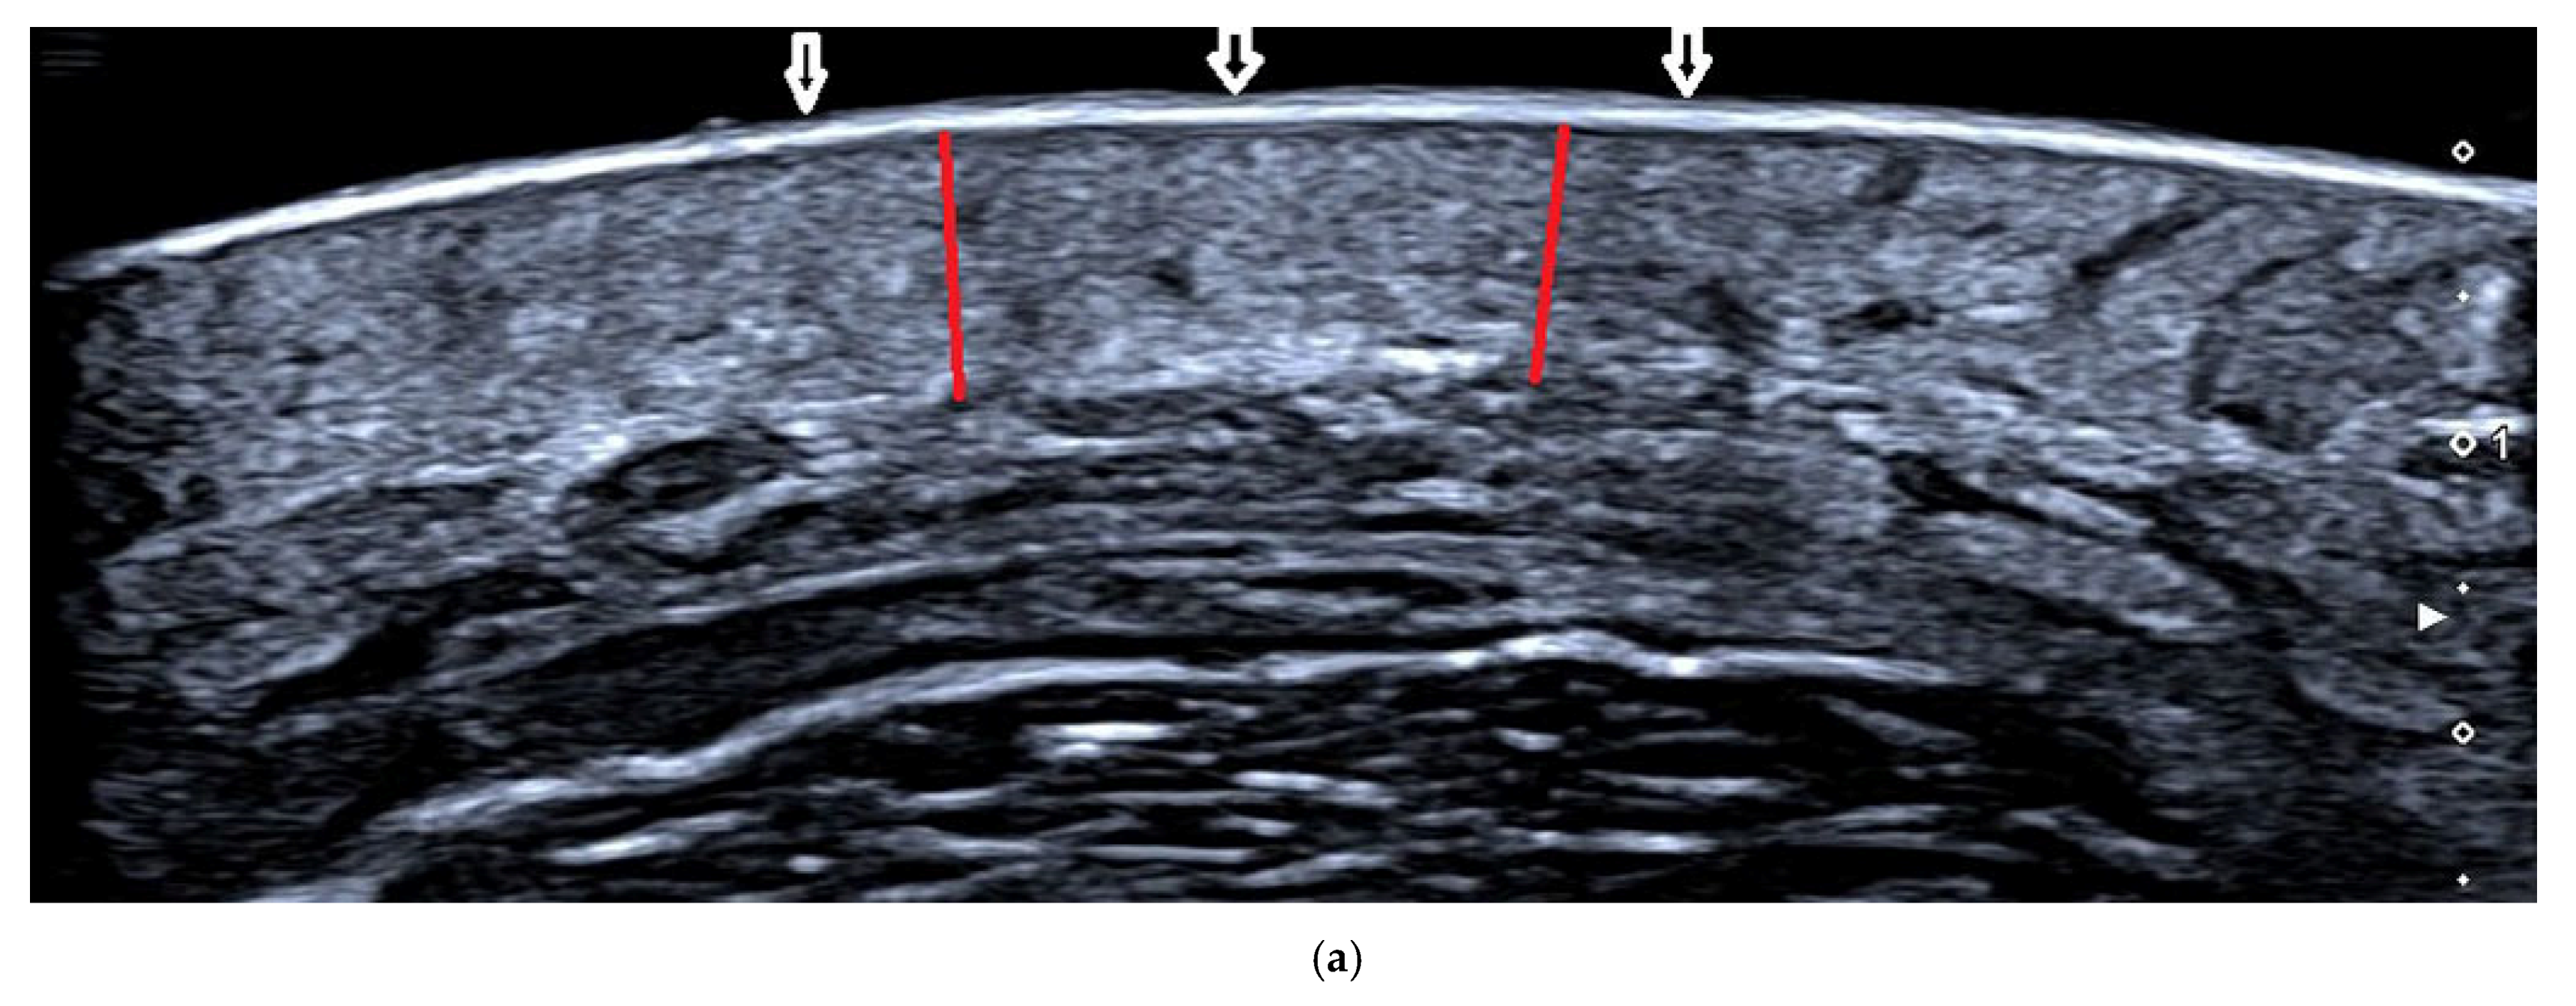

2.4. Ultrasound and Histopathological Evaluation

3.2. Ultrasound Assessment of Dermal Thickness

| Dermal Thickness (mm) | AFL | AFL+MTX | p Value |

|---|---|---|---|

| Before | 1.723 (1.352–2.382) | 2.084 (1.653–2.383) | / |

| After | 1.589 (1.206–2.296) | 1.800 (1.393–2.154) | / |

| Δd | 0.138 ± 0.085 | 0.323 ± 0.205 | 0.016 |

| p value | 0.001 | 0.001 | / |